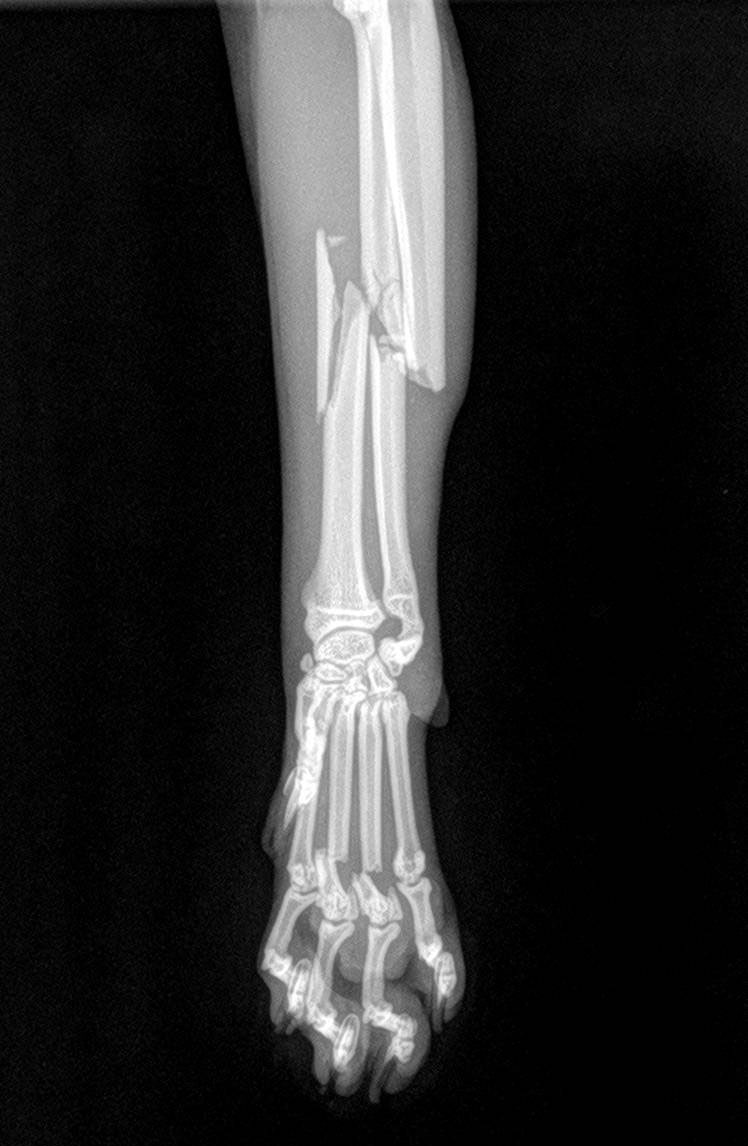

Chirurgie orthopédique